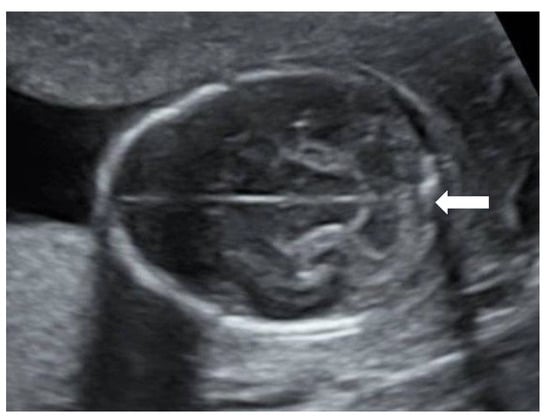

A 27-year-old primigravida was referred to the outpatient clinic of our hospital at a gestational age (GA) of 17 + 3 weeks following detection of a fetal unilateral hydronephrosis by the peripheral gynecologist. Ultrasonography demonstrated a duplex collecting system in the left kidney with hydronephrosis of the cranial pole, moderate dilatation of the upper pole ureter, and mild dilatation of the lower pole ureter. The cerebellum at that time showed a minimal posterior curving (

Figure 1), but no distinct banana-sign. Inspection of the spine was inconspicuous. The patient was reevaluated in our center at 24 weeks GA. The hydronephrosis of the upper pole of the left kidney remained stable. However, the cerebellum presented a banana-shape with herniation of the hindbrain onto C2 and minimal lemon-sign of the skull (

Figure 2). The lateral ventricles were not dilated. Ultrasound examination of the spine revealed a closed skin except for a minimal fistula in the sacro-coccygeal region (